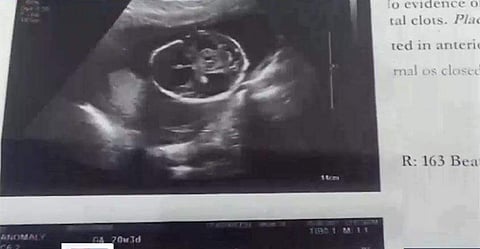

പാറശാല ചെറിയകൊല്ല സ്വദേശി നിഷയുടെ ഗര്ഭസ്ഥ ശിശുക്കളാണ് മരിച്ചത്. പാറശാല സര്ക്കാര് ആശുപത്രിയില് ചികില്സ തേടിയ നിഷയ്ക്ക് ആശുപത്രിയുമായി ഔദ്യോഗിക സ്കാനിങ് കരാറുള്ള വിന്നീസ് ലാബില് പരിശോധനയ്ക്ക് കുറിച്ചു നല്കി. ആദ്യ സ്കാനിങ്ങുകളില് ഒരു കുട്ടിയെന്നായിരുന്നു പരിശോധനാഫലം. അഞ്ചാം മാസത്തില് അസ്വസ്ഥതകള് തോന്നിയതിനേത്തുടര്ന്ന്് മറ്റൊരിടത്ത് പരിശോധന നടത്തുകയും ഇരട്ടക്കുട്ടികളാണെന്ന് ബോധ്യപ്പെടുകയും ഒരു കുട്ടി അബോര്ഷനായതായി മനസിലാക്കുകയും ചെയ്തു.

ഇവരുടെ നിര്ദേശപ്രകാരം എസ് എ ടിയിലെത്തി പരിശോധിച്ചപ്പോഴേയ്ക്കും രണ്ടാമത്തെ കുട്ടിക്കും ജീവന് നഷ്ടപ്പെട്ടിരുന്നു. ഇതേത്തുടര്ന്ന് നിഷയുടെ കുടുംബം പൊലീസിലും പാറശാല ആശുപത്രി സൂപ്രണ്ടിനും ഡി എം ഒയ്ക്കും പരാതി നല്കി